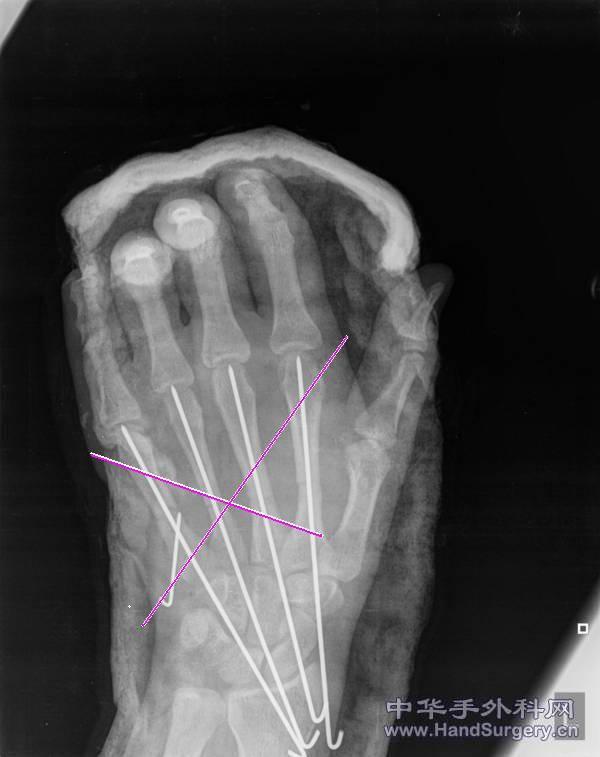

术中拍片

我会交叉打,当然有“C”臂辅助会更好打一点

见红线